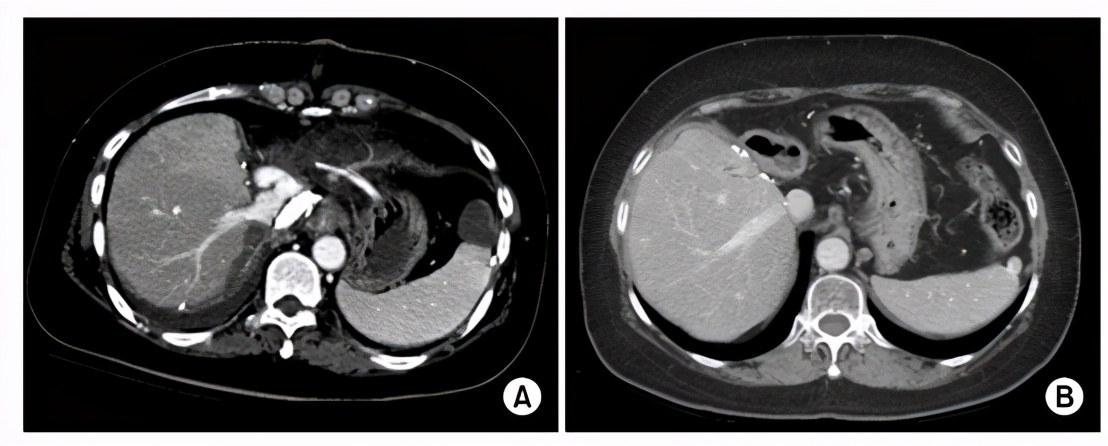

这个病例随访13年都没有发现肿瘤复发,患者生活质量完好。

在没有其它现实的治疗方法面前,为了挽救她的生命,患者在2008年接受了活体肝移植,病人的姐姐为她捐献了部分肝脏,右半肝的活体肝移植手术非常顺利,术后曾经有过一次短暂出血,通过介入治疗获得解决。病人在移植之后,采用他克莫司进行免疫抑制治疗,至今已经随访了13年,都没有发现任何的病灶转移,达到了长期的存活。

移植肝长期存活的CT图像